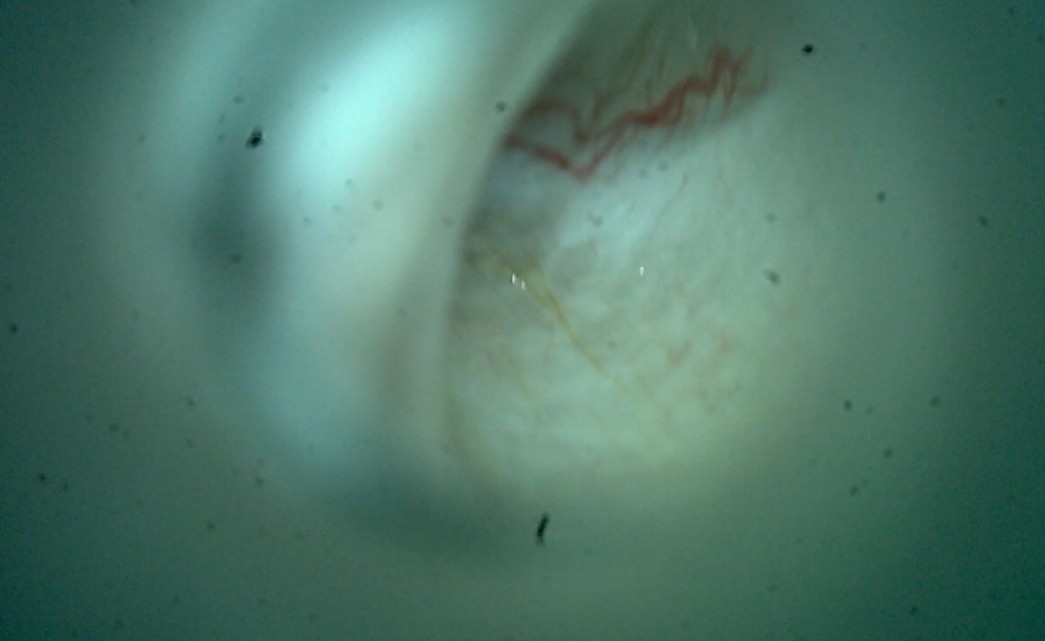

검진 과정에서 송곳니 주변에 치주염 소견이 확인되어 보호자분과 충분한 상담을 진행한 후, 향후 염증의 재발과 통증을 예방하기 위한 예방적 발치까지 함께 진행했습니다.

이번 아이의 경우도 종합검진 중 치아 문제를 새롭게 발견한 것이 아니라, 과거 본원에서 발치 치료를 받은 이력이 있었기 때문에 원장님이 해당 내역을 숙지하고 있었고, 보호자와 충분히 상담한 뒤 송곳니 치주염에 대한 예방적 발치를 결정한 케이스였습니다.

시급히 제거가 필요한 단계는 아니었지만, 향후 염증 악화 가능성과 관리 부담을 함께 고려하여 진행된 치료였습니다.

종합검진은 기본적으로 현재 건강 상태를 넓게 파악하는 과정이며, 치과 질환처럼 마취가 필요한 세부 진단은 포함되지 않습니다. 다만 이번 아이처럼 과거 발치 이력이나 기존 치과 상태를 의료진이 정확히 알고 있는 경우, 종합검진 결과와 별개로 보호자와 충분히 상담하여 개별적인 치료 결정을 내릴 수 있습니다.